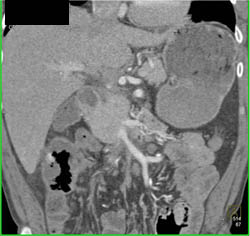

Pancreatic Cancer Encases the PV/SMV